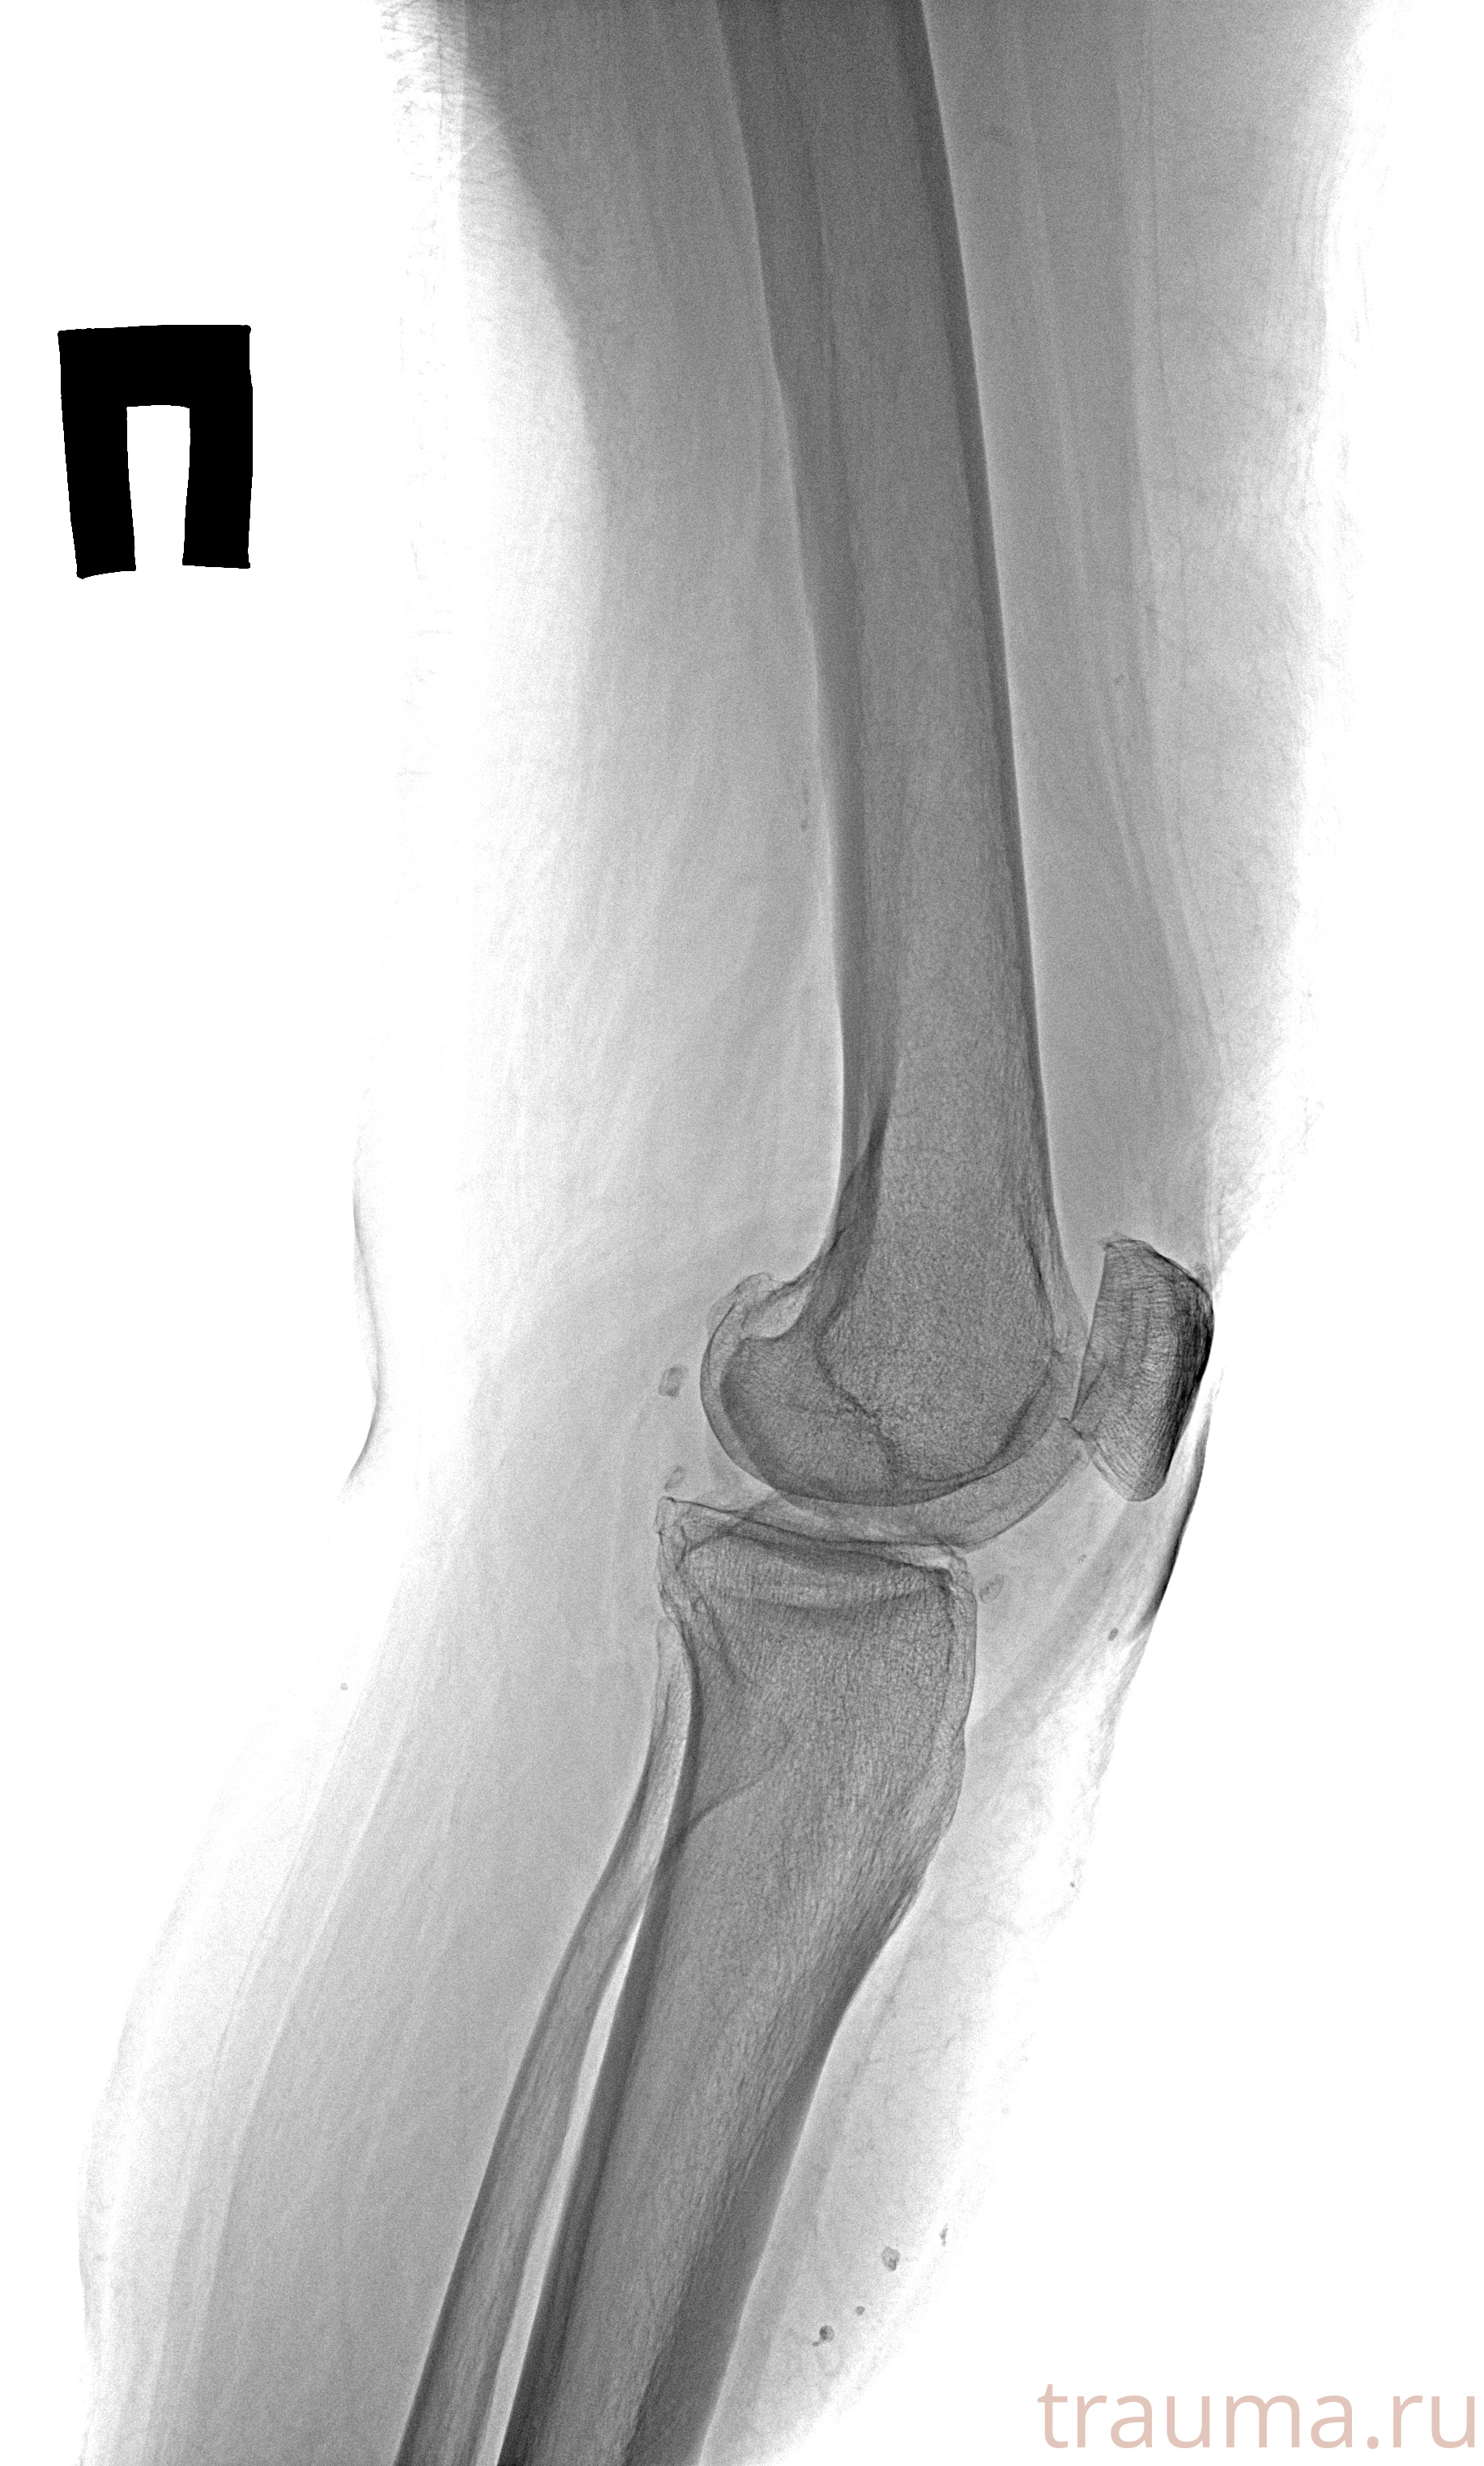

Рентгенограммы

Рентген на дому: по вашему адресу приезжает врач-рентгенолог, травматолог-ортопед с мобильным рентгеновским аппаратом, проводит диагностику травмы или заболевания, делает необходимые рентгенограммы, дает рекомендации по дальнейшему лечению. Получить качественные снимки в домашних условиях возможно благодаря уникальной методике, разработанной МосРентген Центром для института  Склифосовского